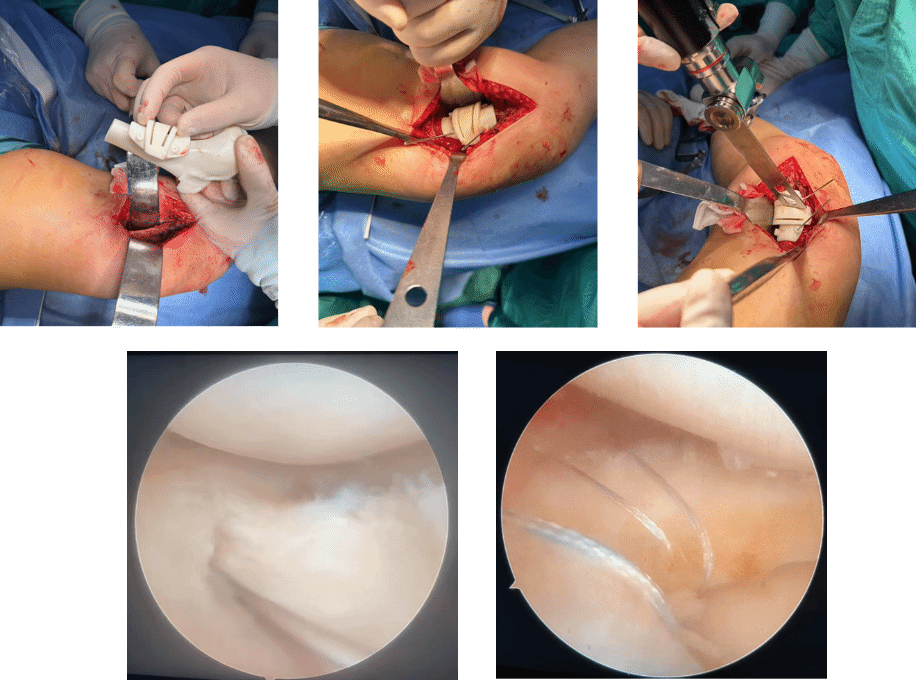

患者为57岁女性,因外伤导致右膝关节畸形40余年,严重影响了日常生活。经多方求医后,患者慕名前来我院运动医学科就诊,入院后科室高度重视,在党晓谦主任的指导下,时志斌教授、倪建龙副教授团队经过详细的术前检查与评估,为其制定个性化的手术治疗方案,通过对患者膝关节影像数据的分析,团队利用3D打印技术定制了符合患者个体解剖特点的截骨导板,从而实现股骨矫正的高度准确性,减少了传统手术中可能出现的误差,确保了股骨矫正后的关节功能得以最大程度恢复。

在截骨过程中,团队依据截骨导板,精准控制合页点位置和截骨角度,动态调整下肢力线至正常范围。为患者提供了个性化的力线矫正和功能改善保障。而对于外侧盘状半月板体部靠近滑膜缘的撕裂,在关节镜下通过Inside-out技术缝合两针,Outside-in技术缝合一针,修复了半月板的损伤。

3D打印技术和关节镜微创技术的结合,为患者提供了更为科学、个性化的治疗方案,提升了治疗效果和患者的术后恢复质量。我院运动医学科将继续致力于先进技术的应用与推广,进一步提升诊疗水平,推动运动医学领域的发展,为更多患者提供专业、高效的治疗服务。